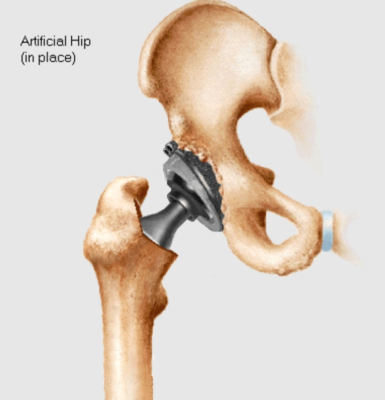

Thiết kế khớp giả và vật liệu

Thành công từ những năm 1960, ban đầu bởi một PTV người Anh Sir John Charnley

Có nhiều loại vật liệu và thiết kế cải tiến theo thời gian

Hiện nay thường gồm phần đùi bằng kim loại bất hoạt (cobalt-chrome và titanium) và phần ổ cối bằng polyethylene đậm độ cao. Một số thiết kế khác như hệ thống kim loại/kim loại và các hệ thống sử dụng bề mặt bằng gốm sứ.